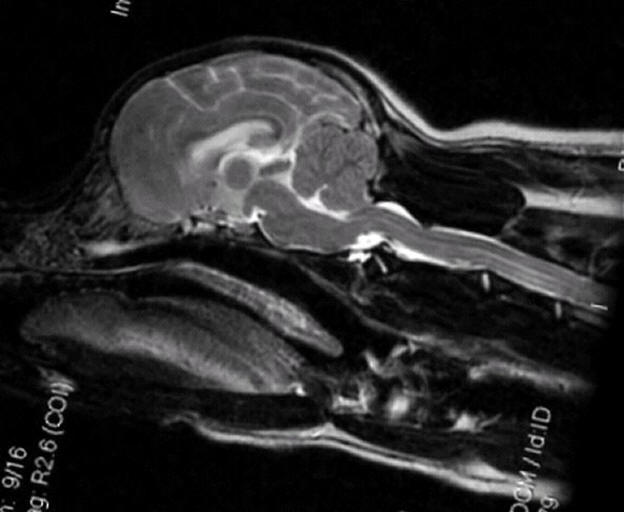

Age Unknown

Moderate malformation/squashing of

cerebellum

Herniation of cerebellum

Medulla kinked/squashed

Syrinxes the entire length of the spinal

cord, some very large